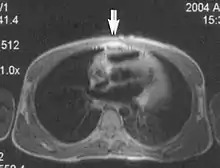

Flow

Flow can manifest as either an altered intravascular signal (flow enhancement or flow-related signal loss), or as flow-related artifacts (ghost images or spatial misregistration). Flow enhancement, also known as inflow effect, is caused by fully magnetised protons entering the imaged slice while the stationary protons have not fully regained their magnetization.[1] The fully magnetized protons yield a high signal in comparison with the rest of the surroundings. High velocity flow causes the protons entering the image to be removed from it by the time the 180-degree pulse is administered. The effect is that these protons do not contribute to the echo and are registered as a signal void or flow-related signal loss (Fig. 2).[1] Spatial misregistration manifests as displacement of an intravascular signal owing to position encoding of a voxel in the phase direction preceding frequency encoding by time TE/2.The intensity of the artifact is dependent on the signal intensity from the vessel, and is less apparent with increased TE.[1]